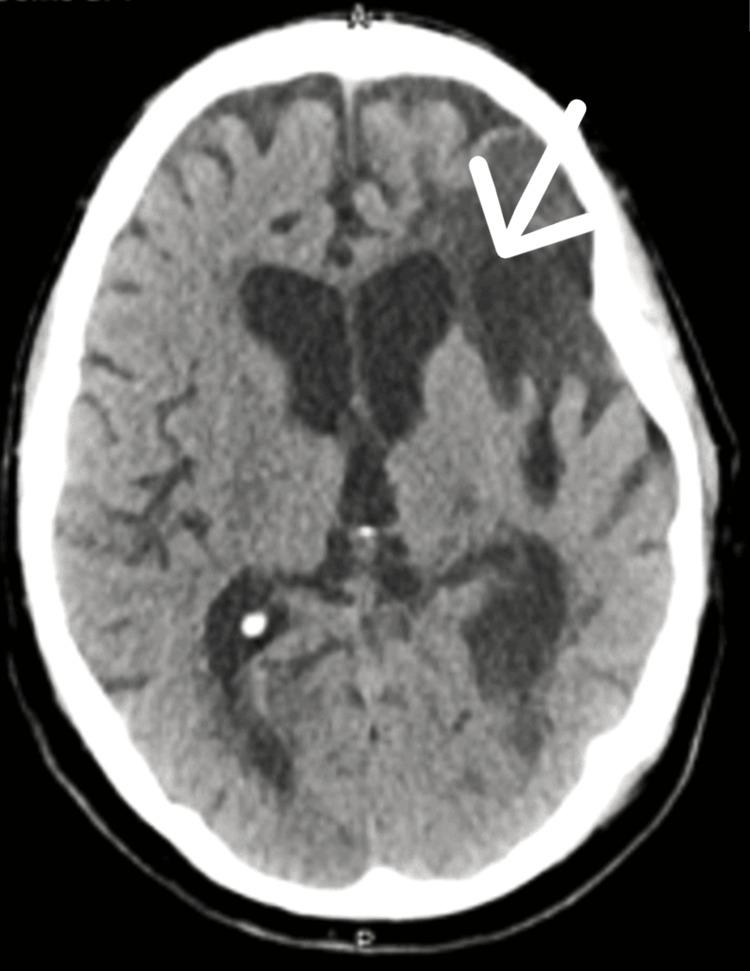

Progressive multifocal leukoencephalopathy (PML) is a rare, often fatal neurological disorder caused by the John Cunningham virus (JCV). It affects immunocompromised individuals, leading to brain demyelination. Diagnosis involves MRI scans and JCV detection in cerebrospinal (CSF) fluid. The mortality rate is high, and current intervention focusses on reversing immunosuppression. We report a patient with chronic lymphocytic leukaemia (CLL) who was diagnosed with PML. He is a 66-year-old male with CLL presenting with multiple falls, right arm weakness, and cognitive impairment. Following MRI head scans and CSF analysis, he was diagnosed with PML. Treatment for CLL was deemed inappropriate due to immunosuppression risk. We initiated Levetiracetam to prevent seizures and considered mirtazapine to prevent viral spread. Mefloquine and cidofovir were considered, but the patient chose not to commence on them. He was discharged with multidisciplinary support. In conclusion, we advise that these stroke-like symptoms may necessitate comprehensive investigation beyond initial CT scans, as exemplified by this case of PML. Relying solely on radiological findings may overlook rare conditions, and clinical skills such as a good history and examination should still be prioritised.